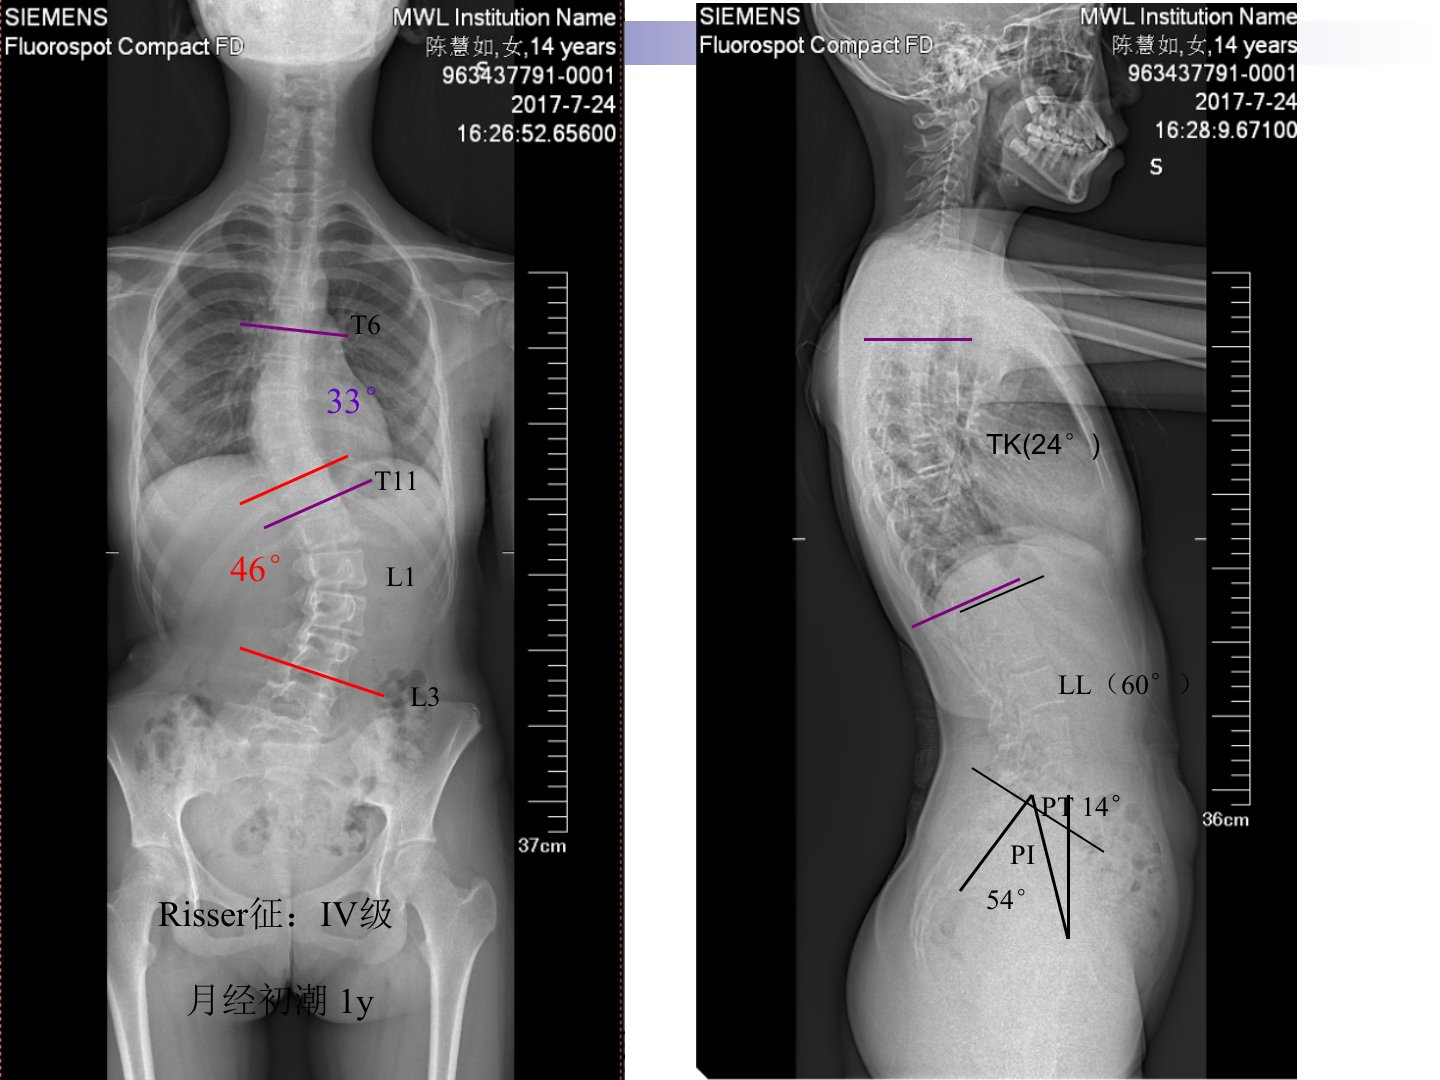

患者主诉腰背部不对称1年余来诊。查体显示其步态正常头部无明显偏斜脊柱胸腰段、腰段向左侧凸右侧肩胛骨稍高但脊柱活动度无明显受限各棘突点无压痛及叩痛。双侧直腿抬高试验正常四肢各肌肌力、感觉正常生理反射存在病理反射未引出。Risser征为IV级月经初潮1年。根据检查结果诊断为青少年特发性脊柱侧弯(Lenke5CN型)。针对此病症制定的手术策略为进行脊柱固定及融合手术其中固定及融合的近端节段为T11远端节段为L3以矫正脊柱侧弯恢复脊柱的正常形态和功能。